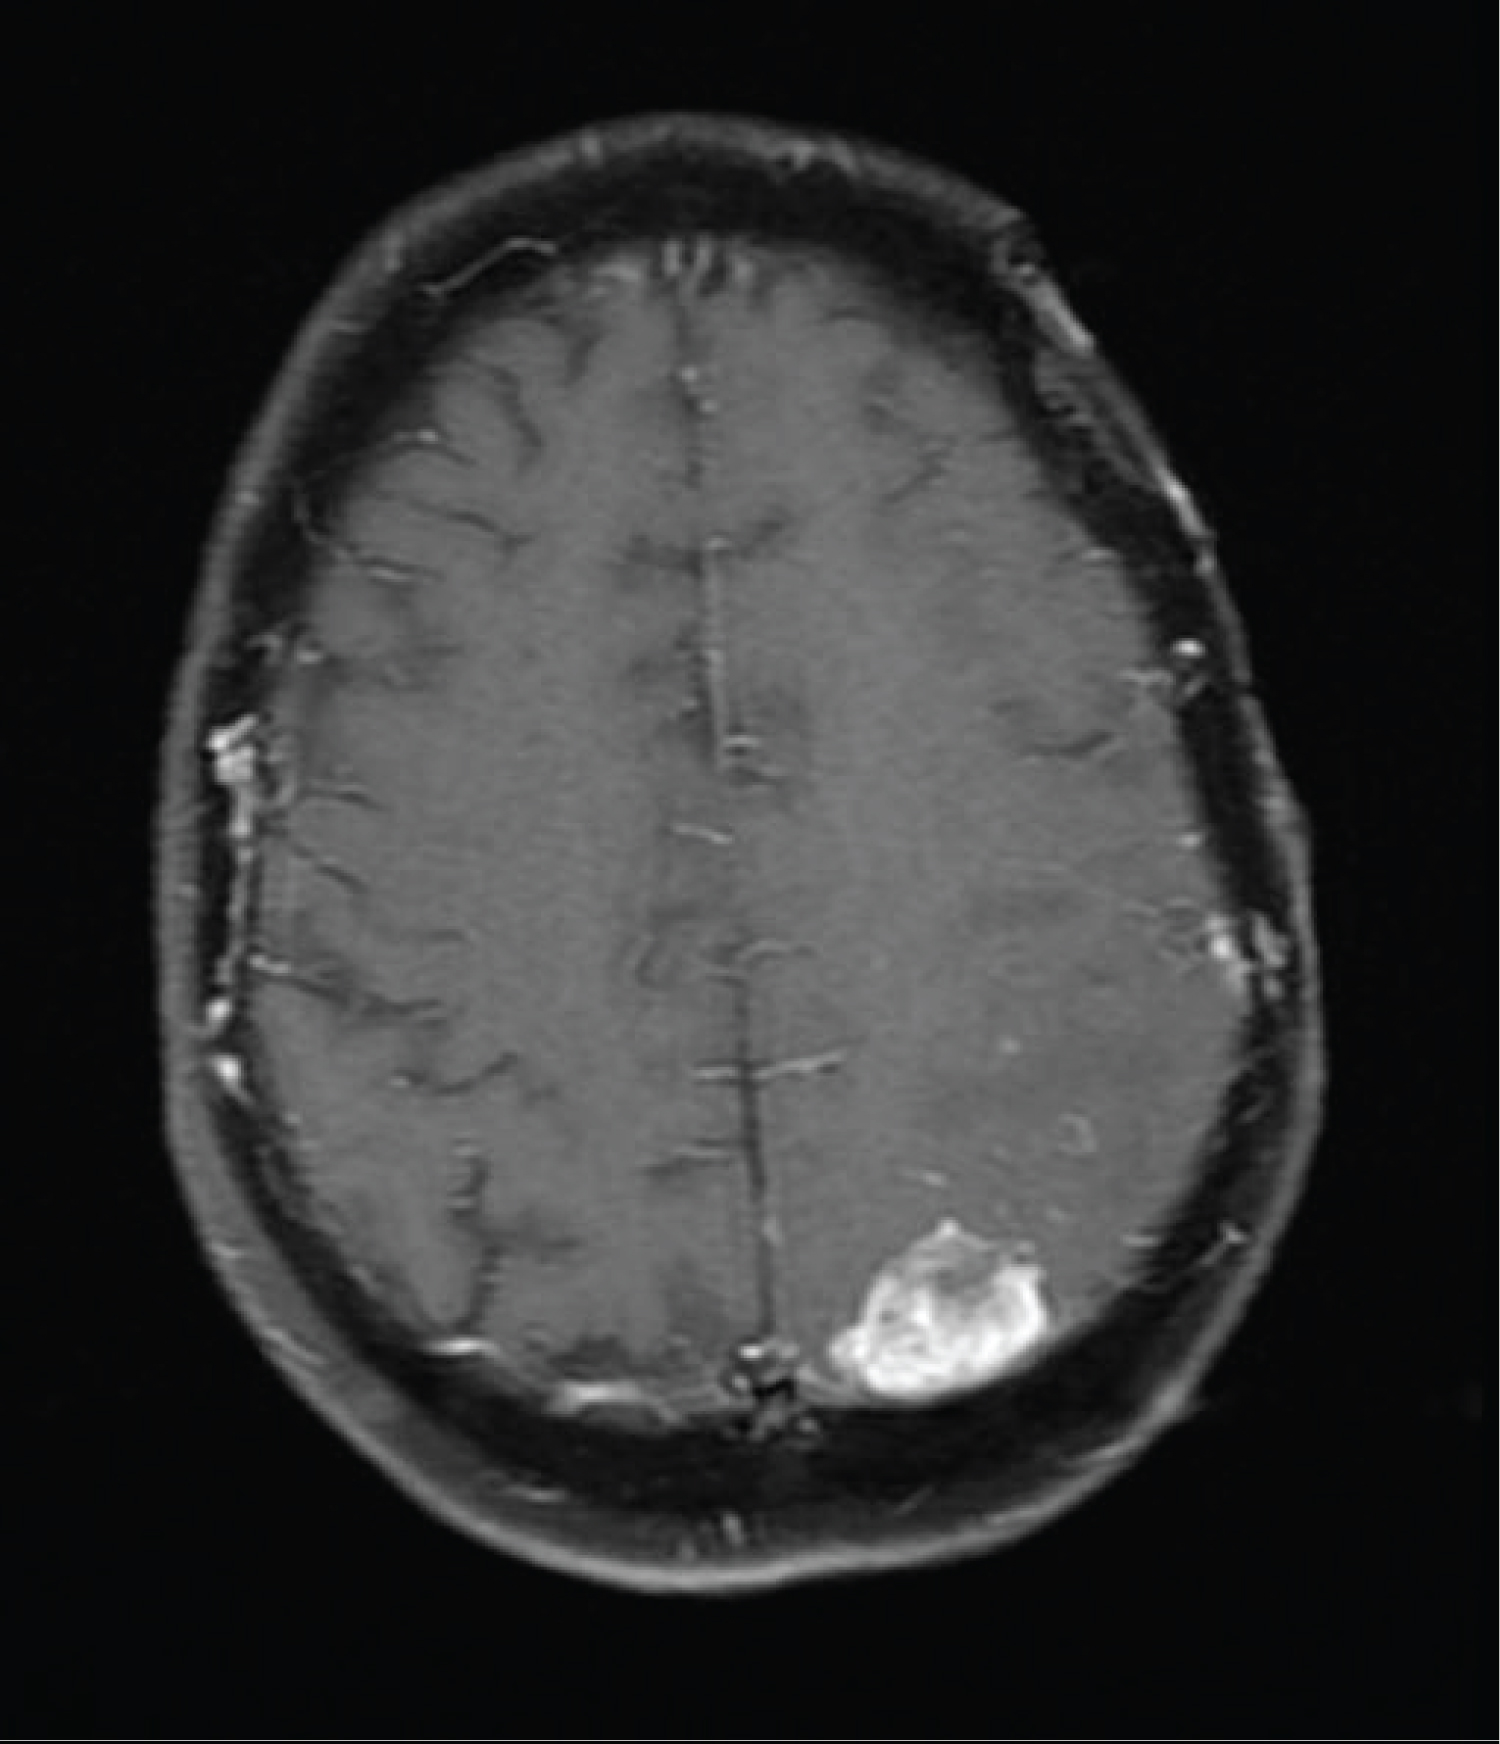

This led to modification of the radiation therapy portal in order to incorporate the third lesion as well as the associated scalp lesion. However, two months after completion of her second course of concurrent radiotherapy and temozolomide, an MRI of the brain revealed a fourth mass with dural contact along the left occipital lobe (Figure 5). She chose for further limited field radiation therapy with concurrent Avastin.

Figure 5: Axial T1 Fat-Suppression images with gadolinium enhancement show a new enhancing mass in the left posterior parietal region with dural contact. View Figure 5